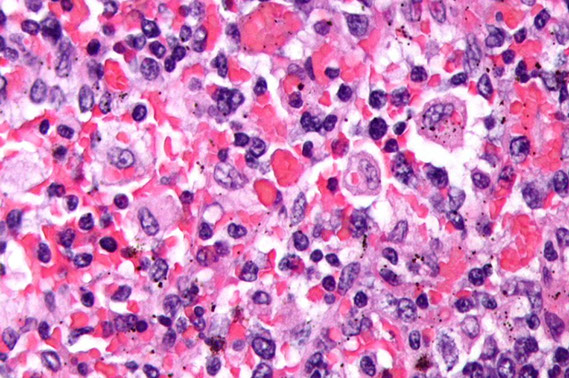

Infectious mononucleosis. Admixed population of cells of varying sizes. In areas where immunoblasts predominated (right) which could be a florid expansions, like large aggregates or sheets of cells with mitotic activity. Spend some time on low power to appreciate the normal architecture, try to find areas with a variety of cell types. Immunoblasts may resemble Reed-Sternberg (RS) cells (inset). [3]